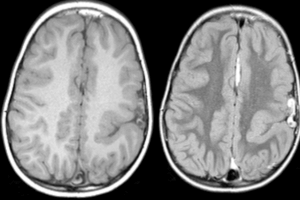

corpus callosum mri

Corpus Callosum Agenesis

In this case, images show a congenital malformation in which the corpus callosum, which connects the left and right cerebral hemispheres, failed to develop. While this abnormality is rare, there are many... Read more »